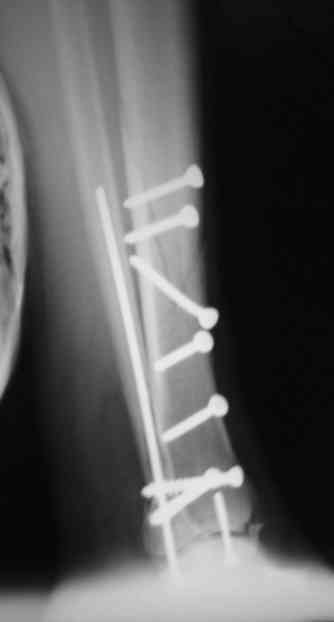

Сегодня прооперировали. Длительность 4-50. Начали как и говорил сверху вниз линейным разрезом - фиксация задне-латерального отломка к проксимальному 2мя винтами, затем "прилепили" к ним передне-медиальный (пришлось повозиться - была интерпозиция и довольно "сложный" винт) - к проксимальному 1 винтом и к задне-латеральному 1 винтом.Кстати на фото видно - у передне-медиального отломка еще осколок в области сустава, несколько смят. Далее началось веселье - второй доступ - задне-наружный к латеральной лодыжке и заднему краю, но оказалось, что задний край больше задне-медиальный (по снимкам было непонятно). Плюс к этому репозиция его мягко говоря сложновата (больной на спине, стол низкий и не поднимается). В общем выставили, фискировали 2мя винтами, на ЭОПе вроде стал, только верх отошел. Латеральную лодыжку заведующий решил интрамедуллярно (не хотел еще винты толкать), сначала 3мм спицей - нестабильно, затем 4мм стержень (не помню по автору) - ОК (кстати в месте перелома мелкая крошка - дефект до 5х7 мм по кортикалу). Ну медиальная лодыжка стандартно - третий разрез - винт 3,5 мм. Визуально все стабильно. На Р-контроле - видна небольшая ступенька заднего края по одному из контуров.

Рентгенограммы

Нельзя ли попросить снимки именно голеностопного сустава. Представлены снимки голени в нижней трети.Сустав фактичеси не виден.

Александр, если вы имеете в виду послеоперационные Р-граммы - то это все что есть. А сустав виден достаточно, чтобы оценить то что есть

Есть подозрение, что имеется ступенька заднего края, внутренняя лодыжка оттопырена. Взаимоотношения в суставе важнее, чем точная репзиция диафиза.